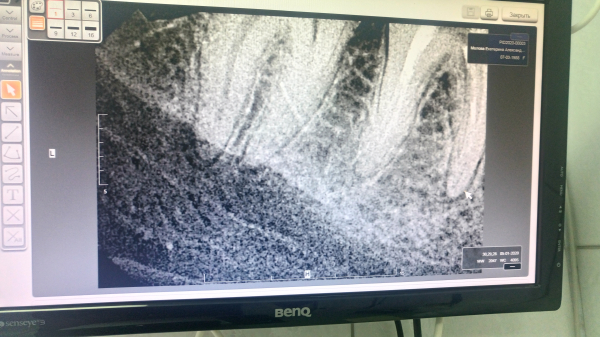

Без клинического осмотра сложно определить однозначно причину. Похоже, в области пролеченного зуба имеется периапикальное воспаление. В области дистального корня соседнего зуба, также определяется разрежение костной ткани. Исходя из снимка, сложно судить, так как возможно наличие артефактов. Причиной онемения может быть воспалительный процесс в области нервных окончаний.